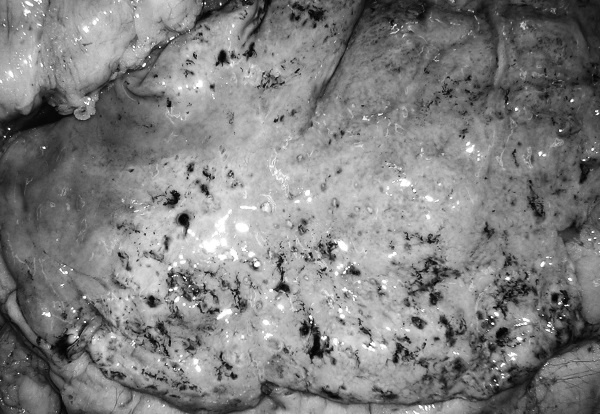

В посмертном эпикризе указан Основной диагноз: последствия ОНМК от 2008 года. ИБС. СН 2. ПИКС. Фоновое: СД 2-го типа, сопутствующее: хронический пиелонефрит. Осложнения: внебольничная пневмония. На секции: ![]() Рис. 31. Последствия перенесенного ОНМК ![]() Рис. 32. Атеросклероз церебральных артерий ![]() Рис. 33. Постинфарктный кардиосклероз ![]() Рис. 34. Гипертрофия миокарда левого желудочка ![]() Рис. 35. Признаки ХСН: мускатный фиброз печени ![]() Рис. 36. Пневмония ![]() Рис. 37. Признаки хронического пиелонефрита Анализируя данный клинический пример, необходимо отметить следующее. 1. Социальный статус. Социальный статус, за исключением указания на участие в ВОВ, не обозначен. 2. Наблюдение на дому. Полное несоблюдение регламента наблюдения ДИП. Клинический диагноз. Записи в амбулаторной карте нет. При этом диагноз должен быть следующим. Основной: последствия ОНМК от 2008 года. ИБС. Постинфарктный кардиосклероз. Фоновое: гипертоническая болезнь 3-й ст., 3 ст. риск 4. СД 2-го типа. Осложнения: длительная иммобилизация. Внебольничная пневмония. НК 2. Хронический пиелонефрит. Анемия. 3. Обоснованность назначения лекарственных препаратов. Терапия СД проводилась вне соответствия с клиническими рекомендациями, контроль за уровнем гликемии не осуществлялся, лечение анемии отсутствовало, вместе с тем при отсутствии подтвержденных данных за пиелонефрит были назначены антибиотики. Таким образом, наряду с указанными замечаниями врач не оценил тяжесть состояния, что не позволило решить вопрос о показанной госпитализации. Приложение № 6 – алгоритм лечения анемии. Приложение № 7 – самоконтроль уровня глюкозы. Пациентка Ф., 84 года. Умерла в январе 2011 года. Иммобилизирована с марта 2010 года в связи с закрытым переломом лонной и седалищной костей. В карте ежемесячные осмотры терапевта в связи с активами СМП. Причина вызовов: гипертонические кризы и болевой синдром. За год до смерти проведены доступные на дому анализы. В плановом порядке в апреле 2010 году проходила стационарное лечение в терапевтическом отделении. Диагноз при выписке: дисциркуляторная энцефалопатия 2-й ст. ГБ. ИБС. СН 3. ПИКС от 2001 года. Железодефицитная анемия. Закрытый перелом лонной и седалищной костей справа. Амбулаторно после стационара принимала энап Н и винпоцетин. В посмертном эпикризе указан Основной диагноз: 1) дисциркуляторная энцефалопатия 2-й ст. и ИБС. СН 3. ПИКС от 2001 г. НК 2А. Фоновое: ГБ. Сопутствующее: хроническая железодефицитная анемия. Закрытый перелом лонной и седалищной костей от 11.03.2010. ![]() Рис. 38. Повторный инфаркт головного мозга ![]() Рис. 39. Постинфарктный кардиосклероз ![]() Рис. 40. Атеросклероз коронарных артерий ![]() Рис. 41. Проявления НК: мускатный фиброз печени ![]() Рис. 42. Острые эрозии желудка ![]() Рис. 43. Атеросклероз аорты Замечания к ведению больного следующие: 1. Социальный статус. Информации нет. 2. Наблюдение на дому. Посещение терапевта осуществлялось только в связи с активами СМП. 3. Клинический диагноз. Нет правильной формулировки диагноза. При этом правильный диагноз был бы следующим. Основной диагноз: 1) Повторный инфаркт головного мозга. 2) ИБС. Постинфарктный кардиосклероз от 2001 года. Фоновое: гипертоническая болезнь 3 ст., 3 ст. Осложнения: закрытый перелом лонной и седалищной костей от 11.03.2010. Длительная иммобилизация. НК 2. Острые эрозии. Хроническая железодефицитная анемия. Сопутствующие: атеросклероз аорты. 4. Обоснованность назначения лекарственных препаратов: лекарственная монотерапия ГБ эналаприлом неэффективна, что повлекло за собой неоднократные гипертонические кризы и вызовы СМП, нет лечения проявлений ПИКС и анемии. Таким образом, не было оценки тяжести состояния, наличия тяжелой степени АГ у больной с перенесенным ОНМК и инфаркта миокарда, кризовым течением и признаками СН, что требовало госпитализации пациента. Приложение № 8 – ведение больного, перенесшего инфаркт миокарда. Пациентка Б., 95 лет. Иммобилизирована. Карта малоинформативна. Осмотры терапевта 1–2 раза в год, лист впервые выявленных диагнозов не ведется. Анализы отсутствуют. Известно, что наблюдалась с диагнозом ИБС, ЦВБ. Хронический бронхит. ОНМК с левосторонним гемипарезом и перелом шейки бедра без указания давности. В карте имеются указания на пролежни. За последние 2 года до смерти терапевтом были назначены: пирацетам, предуктал, мексидол, проведен курс ЛФК на дому. Посмертный эпикриз отсутствует. На секции: ![]() Рис. 44. Последствия перенесенного инфаркта головного мозга ![]() Рис. 45. Постинфарктный кардиосклероз |